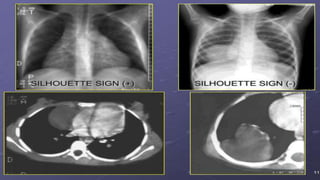

1. Dấu hiệu bóng chồng

Dấu hiệu bóng chồng:

 Hai bộ phận cùng đậm độ, nếu cùng một măt phẳng thì không thấy

ranh giới của nhau.

 Hay 2 bộ phận khác đậm độ cùng mặt phẳng hoặc cùng đậm độ

nhưng khác mặt phẳng thì thấy được bờ của nhau.